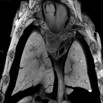

| EFIC imaging of mutant 012-029-NB (E16.5) reveals DORV, right aortic arch, VSD, AVSD, and stenotic pulmonary artery (PA) | Cplane1b2b012Clo/Cplane1b2b012Clo | C57BL/6J-Cplane1b2b012Clo |

| Serial 2D EFIC image stack of mutant 012-029-NB in the coronal view reveals DORV, subaortic VSD, hypoplastic PA, common AV valve, and right aortic arch